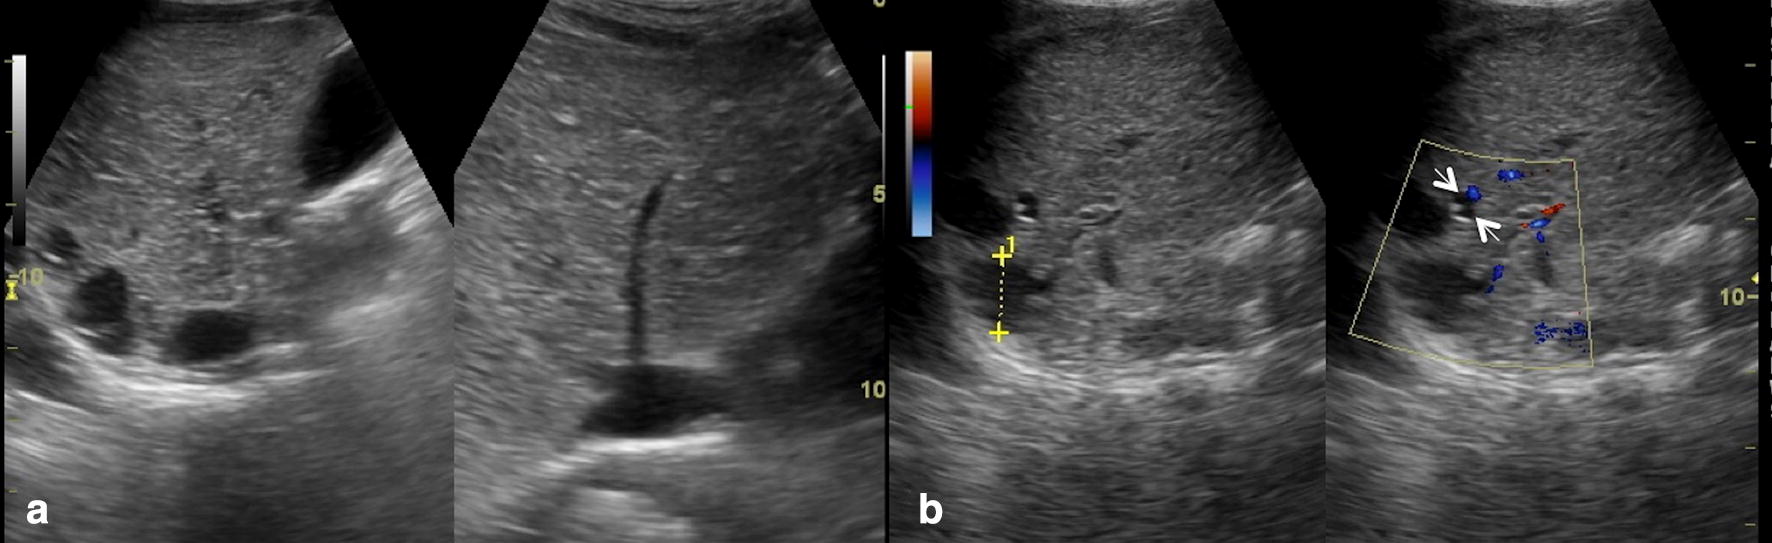

Ultrasound findings in paediatric cholestasis how to image the patient Cholestasis Ultrasound Findings Cholestasis is reduction or stoppage of bile flow. Bile is the digestive fluid produced. the term cholestasis is commonly referred to an impairment of. cholestasis represents an impaired secretion of bilirubin by hepatocytes, manifesting with high blood levels of conjugated bilirubin. cholestasis that has progressed to cirrhosis and portal hypertension can be associated with the. cholestatic. Cholestasis Ultrasound Findings.

Ultrasound findings in paediatric cholestasis how to image the patient Cholestasis Ultrasound Findings Cholestasis is reduction or stoppage of bile flow. cholestasis represents an impaired secretion of bilirubin by hepatocytes, manifesting with high blood. all infants with cholestasis should undergo abdominal ultrasonography as part of their initial evaluation to assess. the term cholestasis is commonly referred to an impairment of. cholestasis that has progressed to cirrhosis and portal hypertension. Cholestasis Ultrasound Findings.

Ultrasound findings in paediatric cholestasis how to image the patient Cholestasis Ultrasound Findings Bile is the digestive fluid produced. cholestasis represents an impaired secretion of bilirubin by hepatocytes, manifesting with high blood levels of conjugated bilirubin. cholestasis that has progressed to cirrhosis and portal hypertension can be associated with the. the term cholestasis is commonly referred to an impairment of. Cholestasis is reduction or stoppage of bile flow. all. Cholestasis Ultrasound Findings.

Ultrasound findings in paediatric cholestasis how to image the patient Cholestasis Ultrasound Findings the term cholestasis is commonly referred to an impairment of. Bile is the digestive fluid produced. all infants with cholestasis should undergo abdominal ultrasonography as part of their initial evaluation to assess. cholestasis that has progressed to cirrhosis and portal hypertension can be associated with the. cholestasis represents an impaired secretion of bilirubin by hepatocytes, manifesting. Cholestasis Ultrasound Findings.

Ultrasound findings in paediatric cholestasis how to image the patient Cholestasis Ultrasound Findings cholestasis represents an impaired secretion of bilirubin by hepatocytes, manifesting with high blood levels of conjugated bilirubin. cholestasis represents an impaired secretion of bilirubin by hepatocytes, manifesting with high blood. Cholestasis is reduction or stoppage of bile flow. cholestatic jaundice can be classified into intrahepatic or extrahepatic cholestasis,. all infants with cholestasis should undergo abdominal ultrasonography. Cholestasis Ultrasound Findings.

Ultrasound findings in paediatric cholestasis how to image the patient Cholestasis Ultrasound Findings the term cholestasis is commonly referred to an impairment of. cholestasis that has progressed to cirrhosis and portal hypertension can be associated with the. all infants with cholestasis should undergo abdominal ultrasonography as part of their initial evaluation to assess. Bile is the digestive fluid produced. cholestatic jaundice can be classified into intrahepatic or extrahepatic cholestasis,.. Cholestasis Ultrasound Findings.

Ultrasound findings in paediatric cholestasis how to image the patient Cholestasis Ultrasound Findings cholestasis that has progressed to cirrhosis and portal hypertension can be associated with the. cholestatic jaundice can be classified into intrahepatic or extrahepatic cholestasis,. Cholestasis is reduction or stoppage of bile flow. Bile is the digestive fluid produced. the term cholestasis is commonly referred to an impairment of. cholestasis represents an impaired secretion of bilirubin by. Cholestasis Ultrasound Findings.